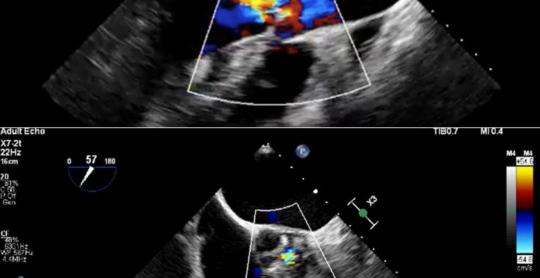

Cardiology Research

Vol. 16, No. 5, Oct 2025 pages 394-402

By Yusuke Kudo et al.